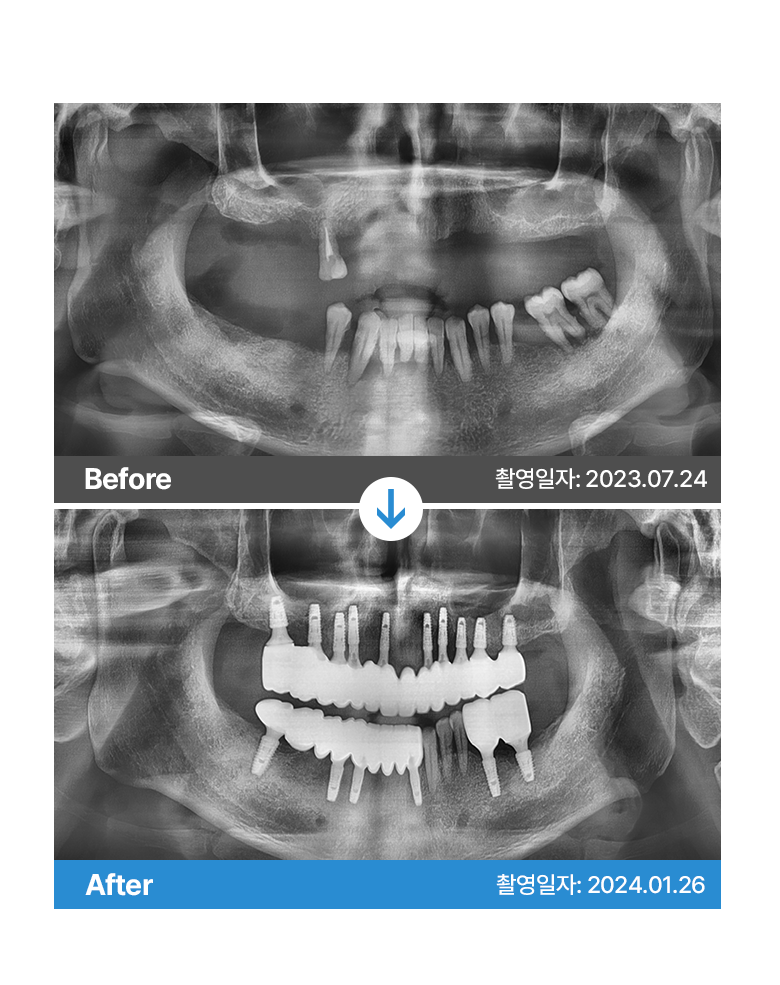

* 본원에서 치료 받으신 환자분의 사례로

환자분의 동의를 얻어 활용함을 안내드립니다.

개인에 따라 결과차이, 부작용 등이 발생할 수 있으므로

의료진과의 상담을 통해 신중히 결정하시기 바랍니다.

* 본원에서 치료 받으신 환자분의 사례로 2차적인 가공이 없으며, 환자분의 동의를 얻어 활용함을 안내드립니다.

개인에 따라 결과차이, 부작용 등이 발생할 수 있으므로 의료진과의 상담을 통해 신중히 결정하시기 바랍니다.